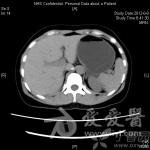

分享【一般资料】 患者36岁女性,体检发现左肾实性占位,无自觉症状。 【辅助检查】 B超:由于保留肾单位手术适应证的扩展,不少恶性肿瘤现在都行肾部分切了,所以术中病理不再是禁忌。有部分术前无法明确良恶性肿瘤的患者会要求选择先行NSS,如果术中冰冻为恶性肿瘤则行根治性肾切除。 【讨论】 1、诊断?2、是否需要行进一步检查?3、治疗方案:观察?手术——保留肾单位手术?肿瘤剜除?单纯肾切除?根治性肾切除?而如果肿瘤小于4cm已进行了NSS,术中冰冻即使是恶性,如果切缘阴性,再行根治性切除是否还有意义?因为据目前文献报道,对于小肾癌NSS比RN的生存率甚至更高。图像为录像剪辑,没有单独采集照相,凑合着看。非常遗憾的是150分钟的手术录像只保存了100分钟(高手的话这个时间可以做两台了)。肾旁前间隙——从肾前筋膜外和腹膜之间的平面分离(部分病人此间隙分离困难)